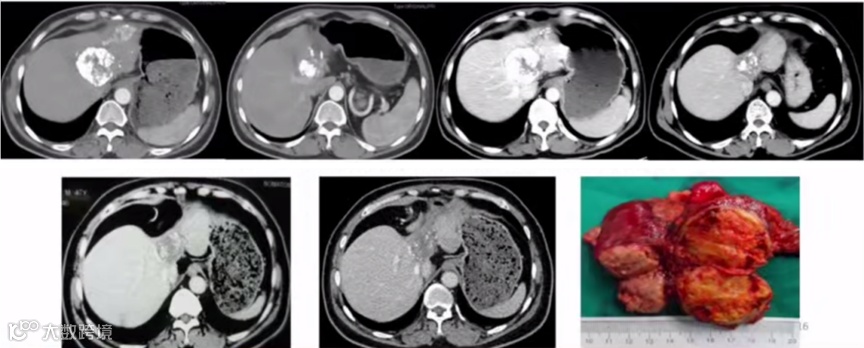

1)病例一:肝细胞癌患者经TACE后转化切除。如图1所示,患者于2010年4月和6月分别进行2次介入,甲胎蛋白从大于1210ng/ml逐渐下降到正常,到2012年7月依然正常。2013年4月,患者AFP又大于1210ng/ml,CT发现左外叶肿块,评估后手术切除,至今存活。

图1. 肝细胞癌患者经TACE后转化切除

2)病例二:肝细胞癌合并门静脉癌栓的患者经TACE后转化切除(图2)。2016年,文天夫教授团队总结临床队列的数据发现,适当增加TACE的次数可以增加转化后的切除率,从而改善预后[5]。

图2. 肝细胞癌合并门静脉癌栓的患者经TACE后转化切除